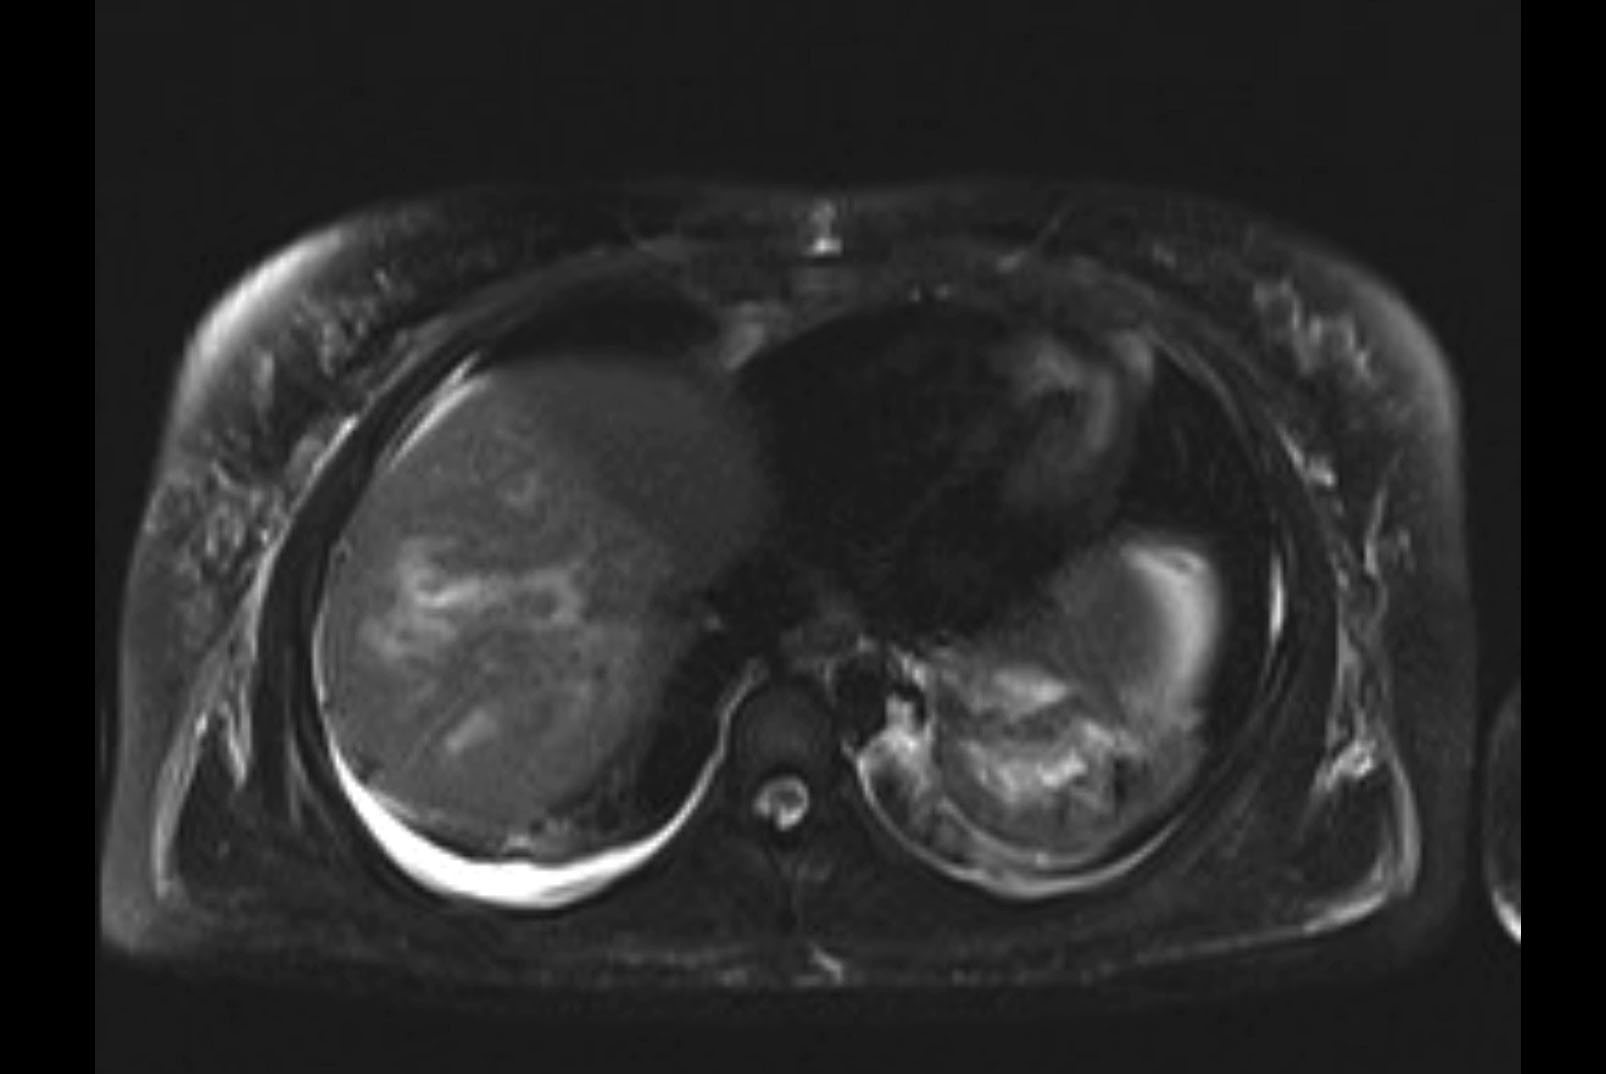

Imaging Analysis

Look through the patient's CT scan to identify any areas of concern for the necessary procedure.

MRI T2

Based on initial findings, which issue(s) would you be most concerned about?